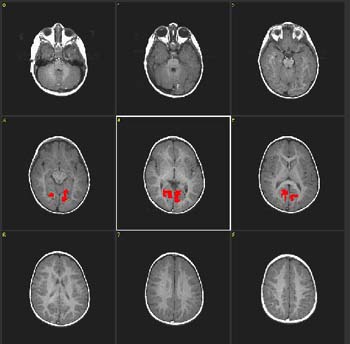

Niña de 2 meses de edad con hidrocefalia |

ACTIVADO: Presentación de la voz de la madre, pregrabada, en la que usa palabras familiares

DESACTIVADO: Nada. Paciente sedado con hidrato de cloral |

| Prueba T |

0,0007 |

3,4 |

| Activación |

Se observa activación bilateral de las circunvoluciones precentrales y la circunvolución temporal superior derecha. La activación de la corteza motora ocurre en el nivel de la representación oral-facial. Se supone que esto está relacionado con el acostumbramiento-desacostumbramiento a la succión de amplitud alta en respuesta a estímulos lingüísticos. Esta respuesta es de gran importancia en la preservación de nuestra especie. |